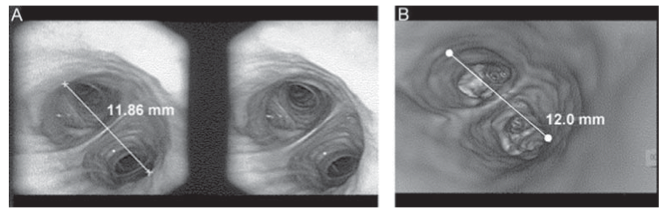

- Se muestra un nuevo método para hacer una medida cuantitativa del calibre de la vía aérea utilizando un fibrobroncoscopio con estereovisión.

- El nuevo fibrobroncoscopio se ha desarrollado por Olympus (BF-Y0006) y consta de dos lentes independientes en la punta lo cual nos permitiría:

- Medida de la distancia espacial entre dos puntos designados en la pantalla

- Medida del total de la longitud de una línea que uniera distintos puntos designados en la pantalla.

- Medida de un área circunscrita por distintos puntos designados en la pantalla.

- Para probar la eficacia del nuevo dispositivo, utilizaron dos pruebas primero utilizaron el fibroscopio para medir el diámetro de tubos de 9,12,15 y 19 mm, resultando unos valores dados por el fibroscopio con estereovisión de 9,9, 12,8, 16,3 y 20,01.

- Posteriomente realizaron la medida de la vía aérea de 12 pacientes con un total de 3 medidas para cada paciente y la compararon con los datos obtenidos por HRCT (Tomografia de alta resolución), obteniendo unos valores medios de 8,66 fibro vs 9,38 con HCRT. Se apreció un correlación fuerte entre ambo tipo de medidas ( r=0,975, p<0,01).

- Concluyen que el nuevo método puede ser válido para la medida del calibre de la vía aérea y el tamaño de lesiones tumorales.